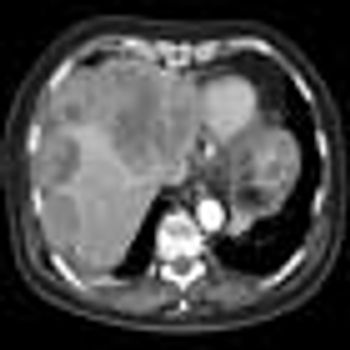

In this review article, the author discusses the use of tyrosine kinase inhibitors in the management of patients with gastrointestinal stromal tumors.